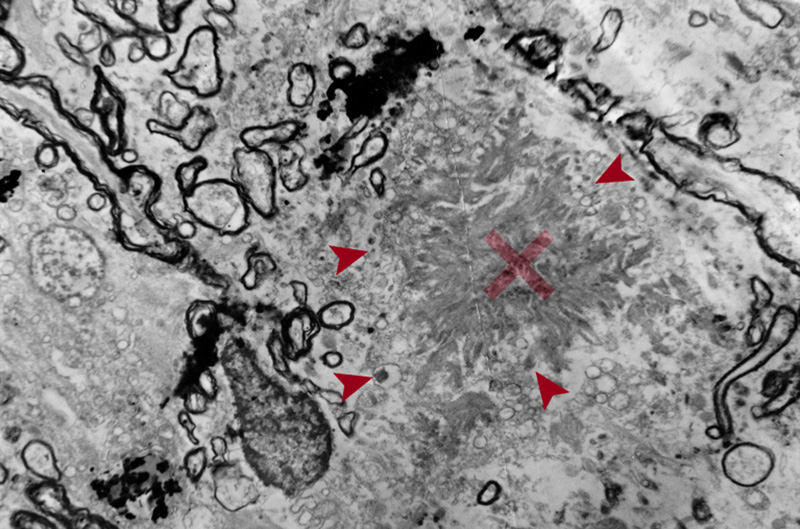

The AD brain often has decreased weight and at least moderate cortical atrophy most marked in the medial temporal lobes (MTLs) with relative sparing the primary motor, somatosensory and visual cortices and enlargement of the lateral ventricles (ex vacuo hydrocephalus). Brain atrophy often involves posterior cortical areas, most notable in precuneus and posterior cingulate gyrus in the preclinical stage of AD [28]. However, none of the macroscopic features are specific to AD, and healthy elderly people often show moderate cortical atrophy especially affecting the frontal lobes, with volume loss of the white matter [29]. Medial temporal atrophy affecting amygdala and hippocampus with enlarged temporal horn is typical of AD (Fig. 1). However, this is also seen in other age-related disorders such as hippocampal sclerosis [30].

Figure 1. Comparison between formalin-fixed brain slices of the left hemispheres (level of posterior hippocampus) of an aged nondemented individual (A) and an AD patient (B). Note the marked atrophy (thinning of the gyri and deepening of the sulci) in B, in particular hippocampal atrophy (arrow in B) with widening of the inferior horn of the second ventricle (asterisk in B). Photographs by courtesy of Simon Fraser and Arthur Oakley.